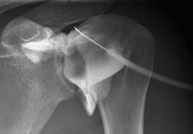

- TMJ X-ray (Temporomandibular Joint)

This technique uses X-ray rendered imaging for examining the temporomandibular joint. Indicated for: trauma, chewing pain, chewing noise, limited mouth opening.

Tècnica que usa els raigs X a través de la qual s'obtenen imatges de l'interior de les extremitats per al seu estudi, especialment dels ossos. Indicacions: traumatisme, infeccions articulars. - RX Artrografia